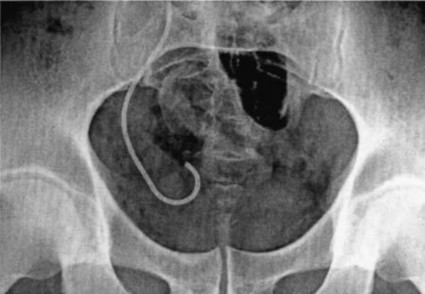

Ống thông niệu quản JJ di chuyển

Ống thông niệu quản có thể di chuyển về đầu gần niệu quản đi vào trong thận hoặc về phía đầu gần niệu quản rơi xuống bàng quang. Theo các báo cáo thì tỷ lệ ống thông niệu quản JJ di chuyển khoảng 8,2 – 9,5 % [153]. Ống thông niệu quản di chuyển có thể do nhiều nguyên nhân khác nhau: như kích thước ống thông JJ không phù hợp, thao tác sai trong quá trình đặt thông (đẩy mạnh đầu dưới của ống thông vào trong niệu quản) [45].

Ống thông JJ di chuyển về đầu xa niệu quản đi vào bàng quang (Nguồn: Dyer R.B., 2002) [48] |